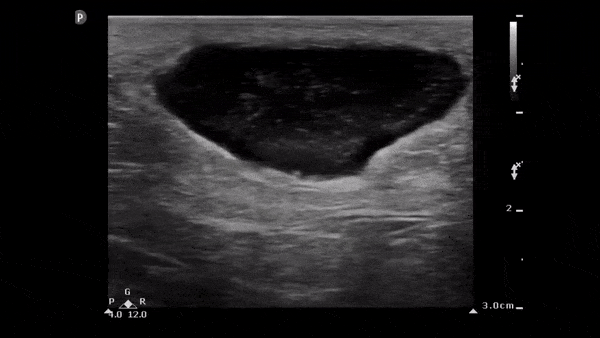

The image below demonstrates a well circumscribed fluid collection in the soft tissue consistent with an abscess. Note the scattered punctate echogenic densities moving within the abscess fluid which suggest high cell/protein content of the fluid. Image obtained from 5 Minute Sono.